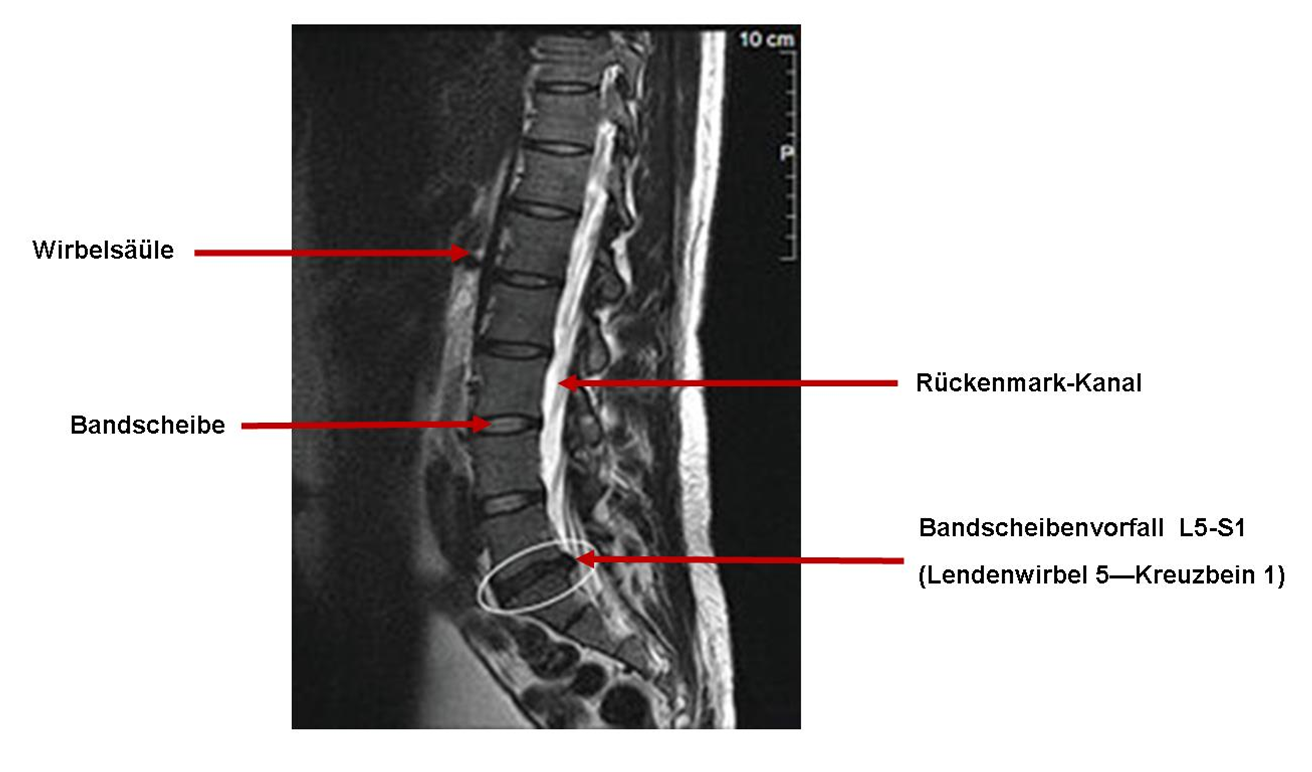

Symptome bei einem Bandscheibenvorfall der Lendenwirbelsäule. Der Bandscheibenvorfall (gelber Kreis) ist massiv und engt sichtbar den Duralsack des Rückenmarks ein

Bandscheibenvorfall Symptome, LWS, BWS, Behandlung und OP. Bandscheibenvorfall L4/5 oder L5/S1 Ob ein Bandscheibenvorfallauf Höhe des 4./5.Lendenwirbels oder auf Höhe des 5.Lendenwirbels und 1.Sakralwirbels vorliegt, kann anhand unterschiedlicher Symptome meist schon ohne weiterführende Bildgebung vermutet werden Falls es also zu einem Bandscheibenvorfall gekommen ist, können nun typische Symptome und Schmerzen auftreten.